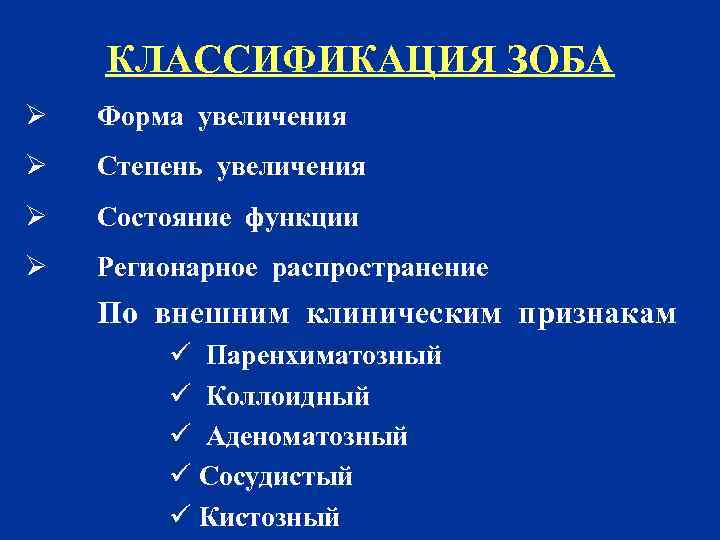

КЛАССИФИКАЦИЯ ЗОБА Ø Форма увеличения Ø Степень увеличения Ø Состояние функции Ø Регионарное распространение По внешним клиническим признакам ü Паренхиматозный ü Коллоидный ü Аденоматозный ü Сосудистый ü Кистозный

КЛАССИФИКАЦИЯ ЗОБА Ø Форма увеличения Ø Степень увеличения Ø Состояние функции Ø Регионарное распространение По внешним клиническим признакам ü Паренхиматозный ü Коллоидный ü Аденоматозный ü Сосудистый ü Кистозный